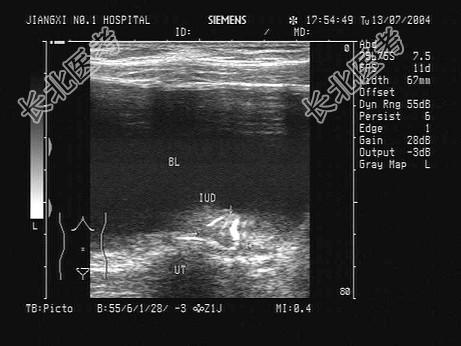

- 单项选择题根据某患者子宫B超检查声像图,下列最可能的诊断为   (   )

B、节育器下移

C、子宫肌层钙化

D、节育器穿孔